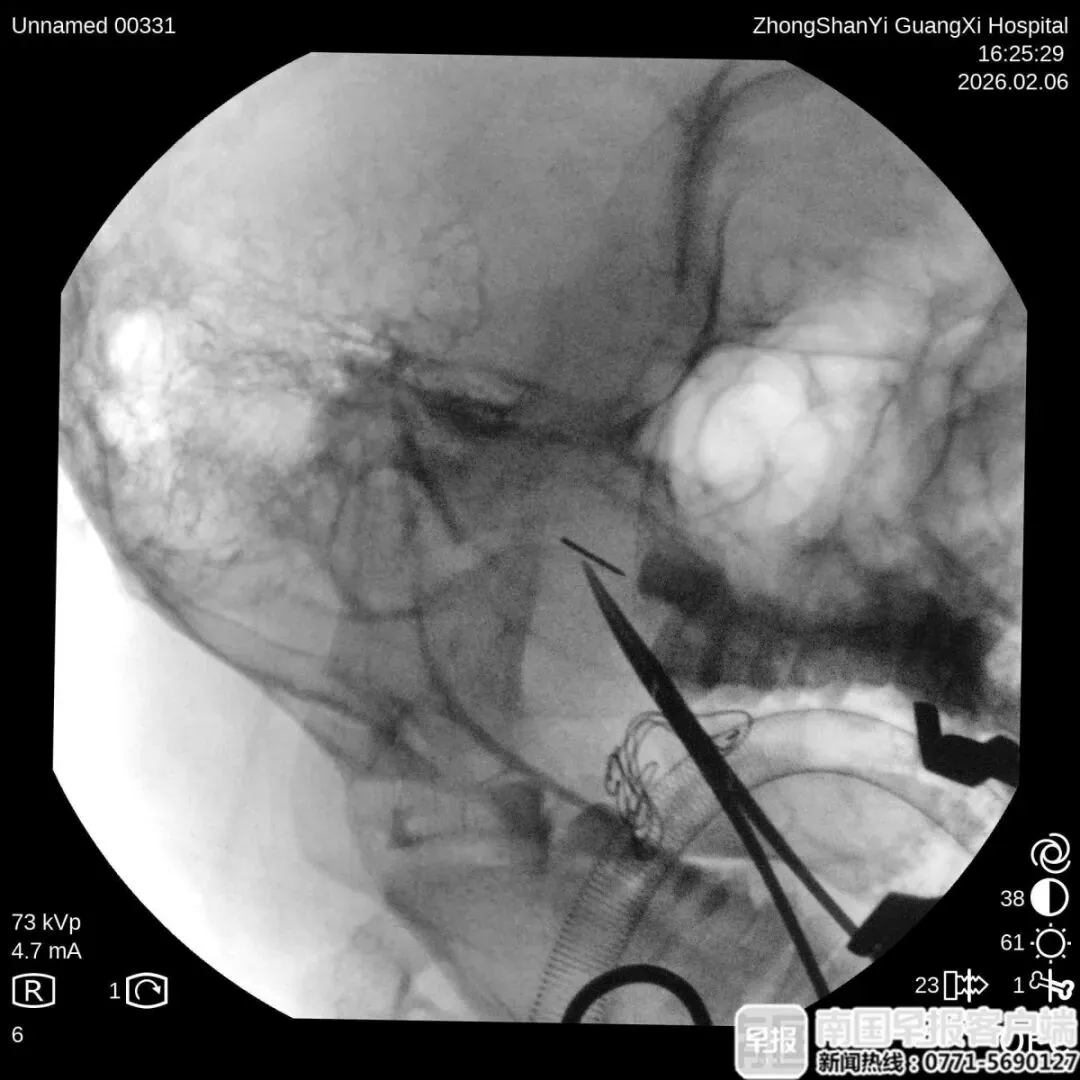

最终,团队为阿诺制订了个性化治疗方案,在气管插管全麻下,借助C臂X射线机多角度定位,为防止断针跟随面部的软组织移动,还使用了高强度磁铁将断针固定。经过30分钟的经口实施手术,医生成功取出断针。